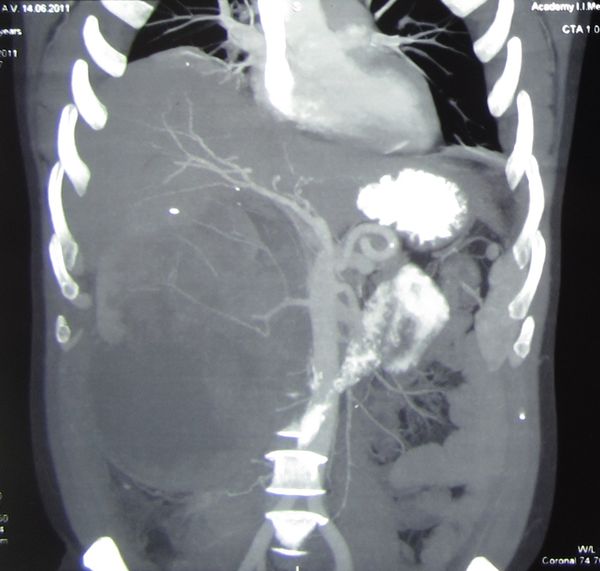

Огромная опухоль правой почки

Гигантская опухоль правой почки. Экстримальная нефрэктомия.